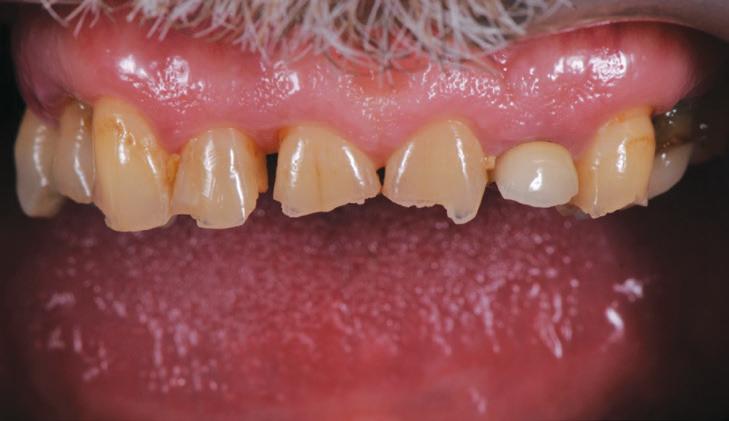

After his examination appointment, it was clear that the two premolars in the upper left quadrant had significant apical pathology and could not be predictably treated. His remaining dentition showed generalised attrition subsequent to dental erosion from gastric reflux, and his lower anteriors showed recession and some loss of periodontal support (Figs. 2, 3).

After discussion with the patient, he decided that he did not want to lose any more teeth and wear removable prosthetics, but he did not have the ability to afford extensive crown and bridgework to restore his dentition. He also requested that his existing (relatively new) crown on the upper left lateral incisor (#22) be retained. With these treatment constraints, it was decided to restore him to a Shortened dental arch1, 2 and that his treatment would occur in phases.

The teeth were cleaned of plaque and the chipped and unsupported enamel was removed (Figs. 4, 5). Fine bevels were placed to facilitate composite adhesion.